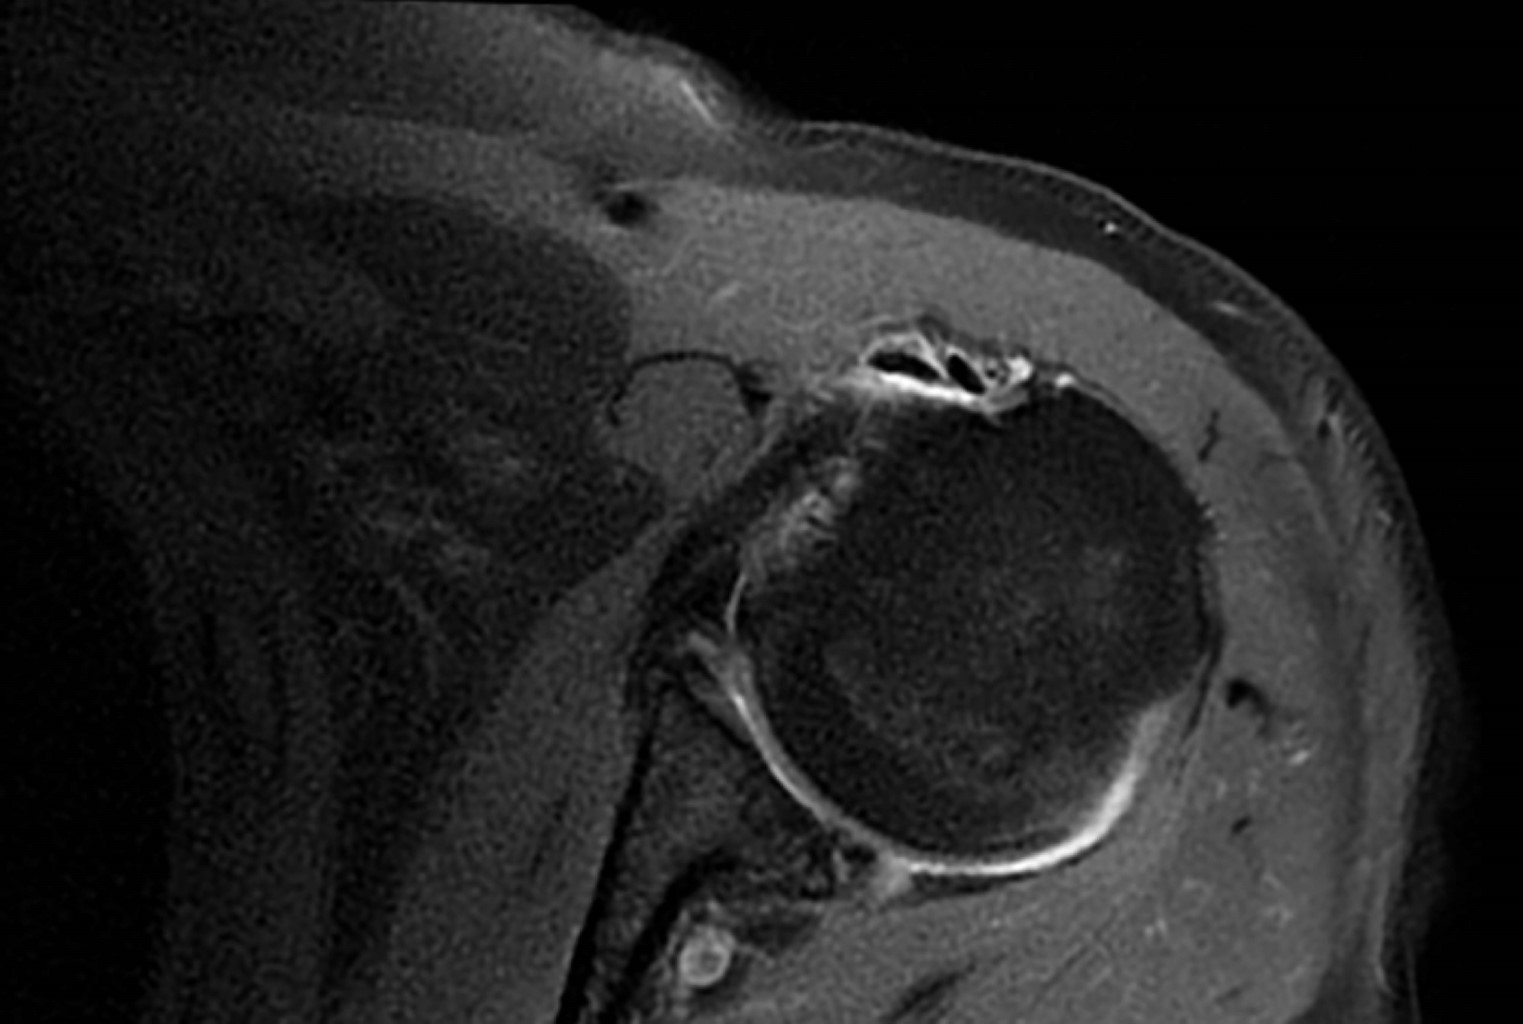

Duplicity of the long portion of the biceps, an anatomical variant poorly described

Articular pain is one of the most common reasons for a medical consultation because shoulder pain is frequent. Anatomical variants may cause confusion during diagnosis among radiologists and surgical treatment for trauma doctors. We will talk about a patient who comes for a magnetic resonance without contrast of the shoulder, for which we found many pathologies, such as the duplicity of the long head of the biceps.

Figure 1